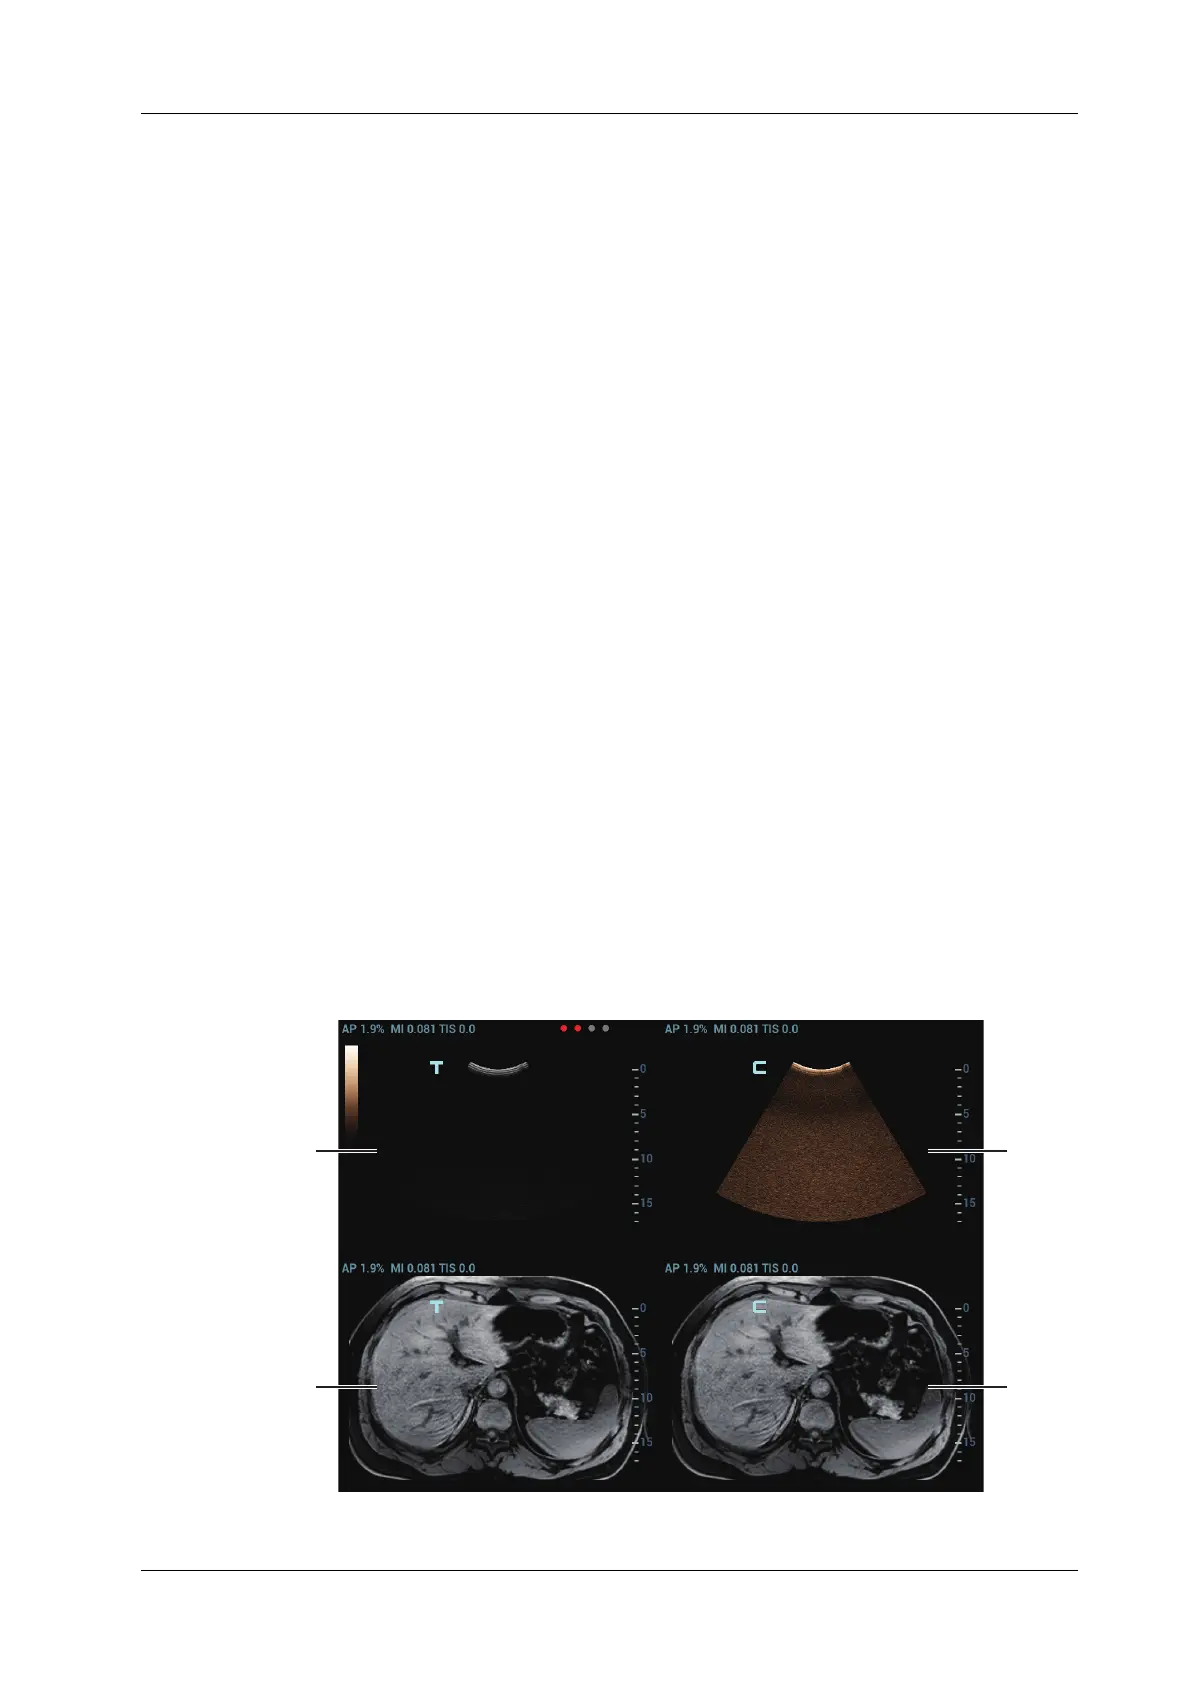

Contrast Fusion Imaging increases the possibility of diagnosing the difficult lesions in the pre-

operation; improves the accuracy to ablating the lesion in the intra-operation; estimates the

therapeutic effect of the target in the post-operation.

1. Tap [Contrast] to enter Contrast Fusion Imaging after the Fusion Imaging is registered.

Set fusion ratio. Adjust the display ratio of two split windows that the contrast image registers

with CT/MR/PET/freehand image.

2. Contrast Fusion Dual Live:

Select [Contrast] > [Dual Live] to adjust the fusion ratio. Adjust the display ratio that tissue

image registers with CT/MR/PET/freehand image (see Window 1 and window 2). Adjust the

display ratio that contrast image registers with CT/MR/PET/freehand image (see window 3

and window 4).